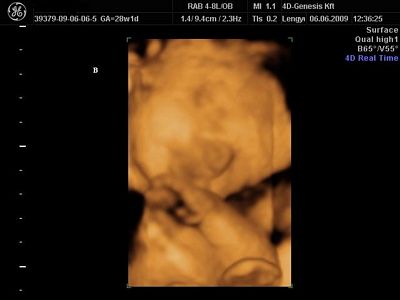

Mi voltunk tegnap 4d-n,ugyanott,mint 16 hetesen,de most sajnos a másik nő volt,hááát,elég nagy a különbség a munkájuk között.Csinált az egy órás uhu alatt 8 képet,az is mind ugyanolyan.Majd felteszem.

Rendben vannak,977 gramm Nonó,és 1170 Balász.5 nap különbség van köztük,Balázs csontra annyi idősnek mérte a gép,mint amennyi,28+1 voltunk tegnap,Nonó 5 nappal kissebb.Viszont érik a lepényem(grannum I-II),sokkal több pihit és kevesebb streszt írtak elő,de azt mondták aggódni ne aggódjak ezen.

És a képek:

Nonó az elsőn,Bazsi a másodikon: